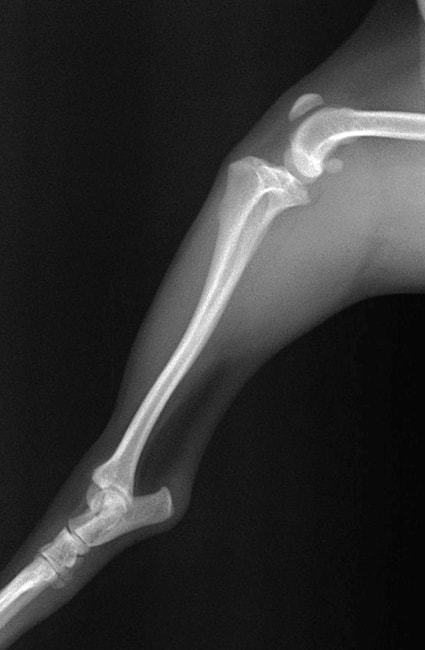

■ 症例20 ポメラニアン 8ヶ月 1.8kg

左右膝蓋骨脱臼 グレードⅢ

2ヶ月前から間欠的跛行が認められ、両膝の膝蓋骨脱臼整復術を行った。

手技は縫工筋及び内側広筋の解放、脛骨粗面の外側転位、滑車ブロック形造溝術、内外側関節包の縫縮を選択し実施した。

右側の膝蓋骨脱臼は上記手技で整復されたものの、左側はそれのみでは膝蓋骨が浮く様子が認められた。その為、PDS縫合糸にて膝蓋靱帯を1糸のみ縫合し、靱帯の縫縮を行った。

膝蓋骨脱臼は膝関節における膝蓋骨の内外側の脱臼と定義されるが、時として単純な内外の脱臼ではなく、膝蓋骨が大きく前方に浮き上がるように脱臼する場合がある。特にトイプードルやポメラニアンといった犬種に多く認められる。

内側脱臼に加えて前方への浮き上がりを矯正する為に、従来より脛骨粗面転移により膝蓋靭帯を外方と下方に引っ張り、固定する方法を選択する。膝蓋骨の前方への浮き上がりが軽度の場合は、従来法ではなく関節包の縫縮で対応していた。しかし、一部の症例で膝蓋骨の動きが悪くなり伸展機構が円滑に機能せずロボット様歩行になるケースがあった。

その為、膝蓋靭帯自体を縫縮する方法を採用した。この方法により、膝関節の伸展機構を妨げず膝蓋骨の軽度の浮きを矯正することが可能となった。

本症例の経過は良好である